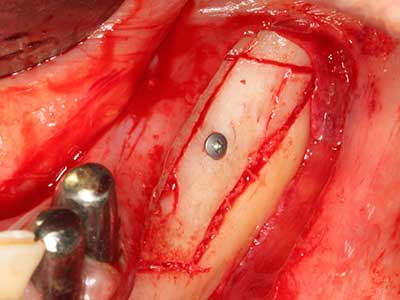

As shown in the past, basically any bone surgery procedure represents a possible indication for piezo surgery. Thus preparation of the mobile segment in distraction osteogenesis (Fig. 23-25) and sandwich osteotomy uses special attachments without endangering the blood supply to the crestal section, which is essential for the success of both techniques (Gonzalez-Garcia, Diniz-Freitas et al. 2008).